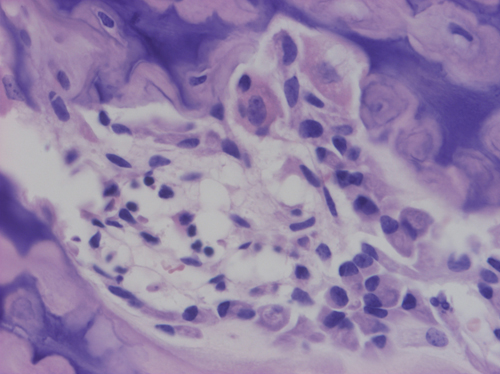

Los osteoclastos (*) son los macrófagos del tejido óseo. Se trata de células multinucleadas perteneciente al sistema mononuclear fagocitario. Son células grandes, poligonales y multinucleadas. Su función fundamental es la remodelación ósea.